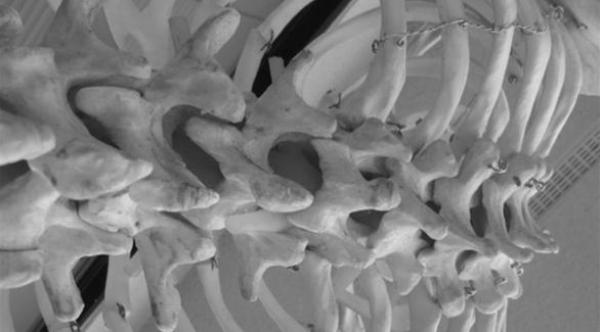

وتزداد كسور العمود الفقري في ألمانيا بسبب ارتفاع معدل الأعمار هناك حيث تصيب هذه الكسور كبار السن بشكل خاص وذلك بسبب تراجع كثافة العظام لديهم حسبما أوضح البروفيسور كريستوف يوستن الذي وصف هذا الارتفاع بأنه "موجة من تسونامي".

وقال المشاركون في المؤتمر إنه تم تطوير العديد من الوسائل والطرق التقليدية الجديدة في علاج خشونة الفقرات وتنكسها وإن من بين هذه الطرق على سبيل المثال ملء الفقرات بالأسمنت.

وأوضح الخبراء أنه أصبح من الممكن اليوم تصحيح حالات الانحراف الشديد في العمود الفقري.